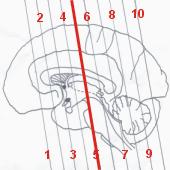

| VÝUKA | |

| Zkoušení 1 | Zkoušení 2 |

| Corpus callosum - truncus |

| Septum pellucidum |

| Fornix - corpus |

| Thalamus |

| Adhesio interthalamica |

| Nucleus subthalamicus |

| Nucleus caudatus - corpus |

| Putamen |

| Globus pallidus |

| Claustrum |

| Capsula interna - crus posterior |

| Ventriculus lateralis - pars centralis |

| Ventriculus lateralis - cornu temporale |

| Nucleus caudatus - cauda |

| Ventriculus tertius |

| Substantia nigra |

| Fossa interpeduncularis |

| Crus cerebri |

| Pars basilaris pontis |

| Pyramis medullae oblongate |

| Hippocampus |

| Sulcus lateralis (Sylvii) |